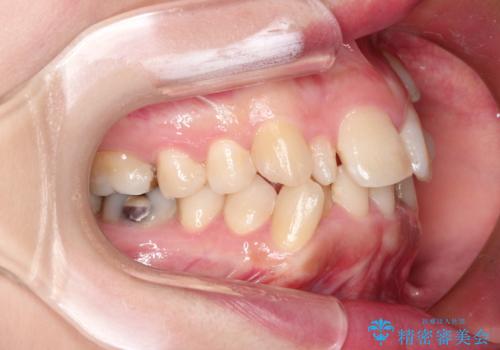

犬歯が変な位置にある 抜歯矯正により正しい位置へ

左上の犬歯が通常の位置より、かなり上方にあり、乳歯の残存と前歯のがたつきがありました。